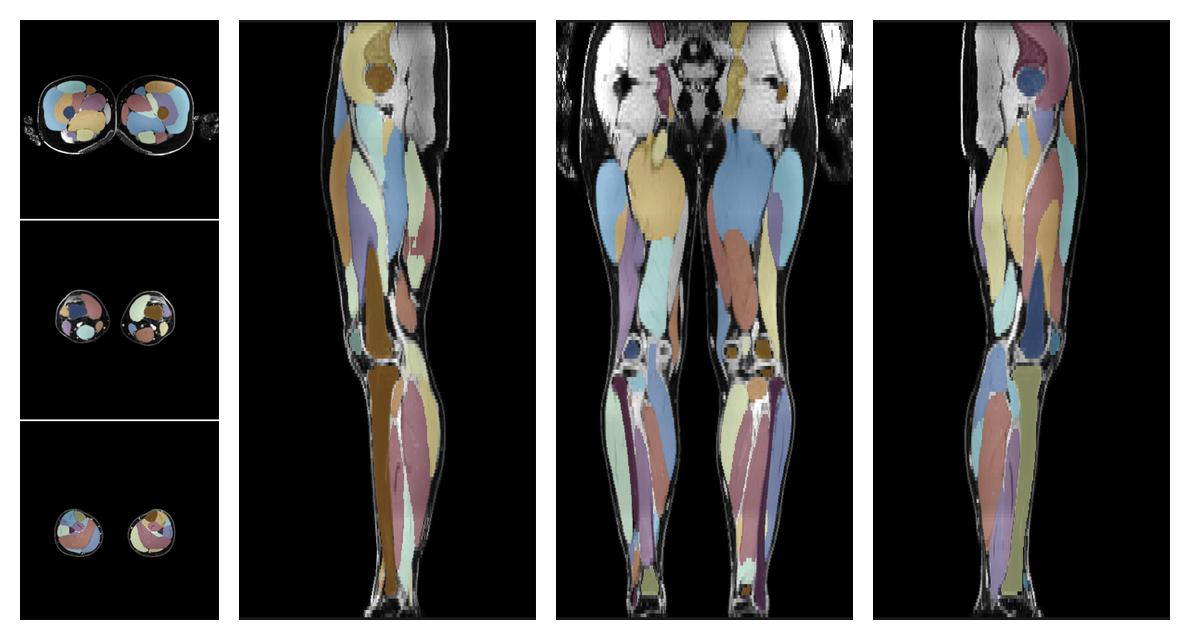

• Automated muscle and bone segmentation.

Overlay of automated muscle segmentation labels on dixon water image.